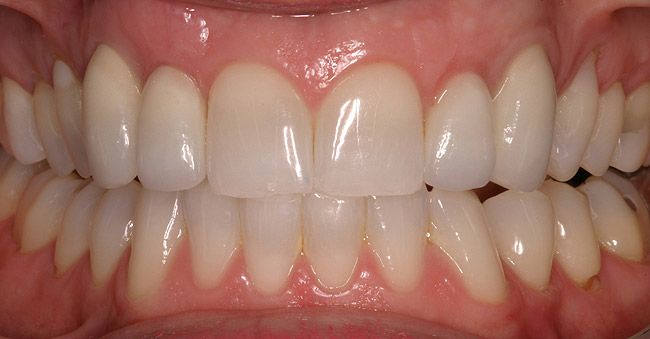

Figure 5e  Completed, porcelain-fused-to-gold implant restorations, custom gold abutments, lingual-set screw-retention, Kerr Extrude¬Æ light-body crown-abutment seal.

Figure 5e

Figure 5f  Completed, porcelain-fused-to-gold implant restorations, custom gold abutments, lingual-set screw-retention, Kerr Extrude¬Æ light-body crown-abutment seal.

Figure 5f

Figure 5g  Completed, porcelain-fused-to-gold implant restorations, custom gold abutments, lingual-set screw-retention, Kerr Extrude¬Æ light-body crown-abutment seal.

Figure 5g

Of all the options presented, when treatment planned and performed to recommended implant surgical and prosthetic guidelines, this option is the most conservative from biological standpoint. The esthetic outcome can be as natural as the tooth it is otherwise replacing (Figure 5).13-15 Patient satisfaction for such successful treatment outcomes is high.16 However, not all patients who are missing a single anterior tooth are ideal candidates for implant therapy. There may be medical contraindications, significant site preparation required, and/or financial constraints. Dental providers may find the resin-bonded or conventional FPD option a more suitable treatment modality with the patient accepting the associated disadvantages and limitations. If this is the case, it is important to have a wider overall treatment outcome picture when comparing the different options.17 From a long-term perspective, few patients perceive real value to either doing nothing or choosing an RPD. Consequently, this leaves the two main contenders: conventional FPD therapy versus single-tooth implant therapy.